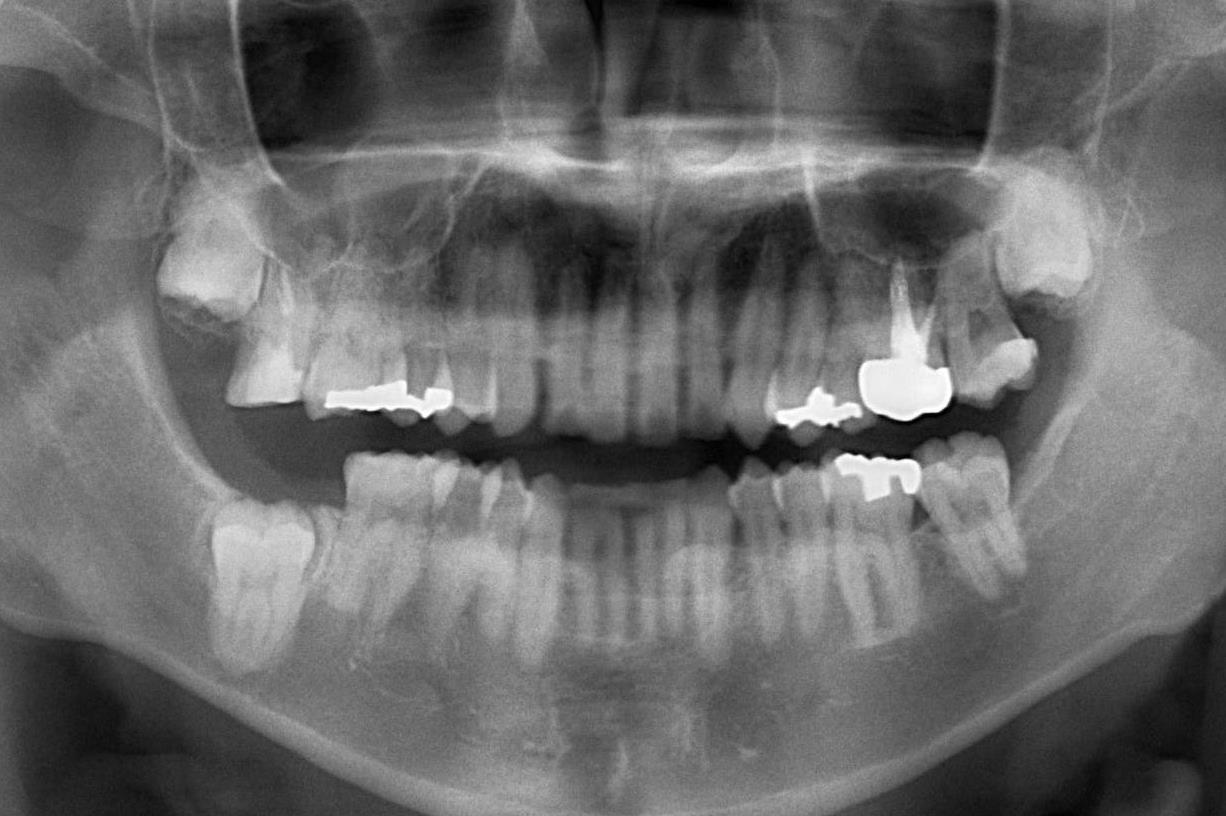

0000001124